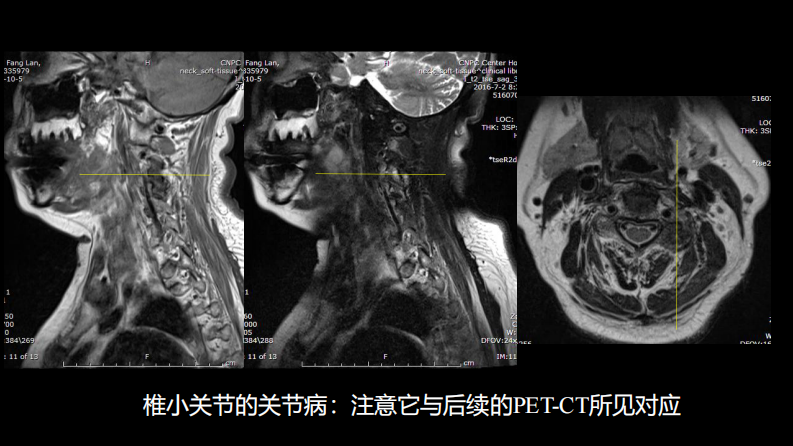

椎体局灶性病变:综合影像学评判.pdf